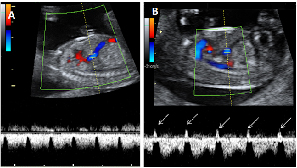

Flujo patológico en el conducto venoso

Doppler en conducto venoso. Registro normal (marcado con la letra A) y registro patológico (letra B), con onda a negativa (flechas).